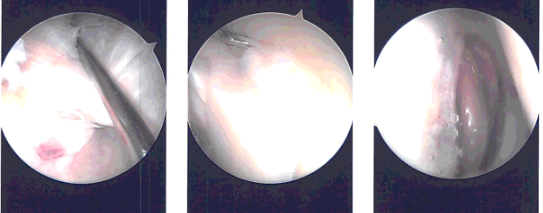

The debridement of the patellofemoral joint was done and chondroplasty was performed with the use of the thermal wand and shaver. Suprapatellar plica was permanent which was removed with the use of a thermal wand.

The scope was entered from the medial portal and instruments were entered from the lateral portal to complete the medial meniscectomy.

Final pictures were taken and saved. The knee was thoroughly irrigated. The knee was drained. Closure was done with use of the # 3-0 nylon. A 9 cc of Naropin 0.5% mixed with 40 mg of Depo-Medrol was injected in the knee.

Intraoperative images